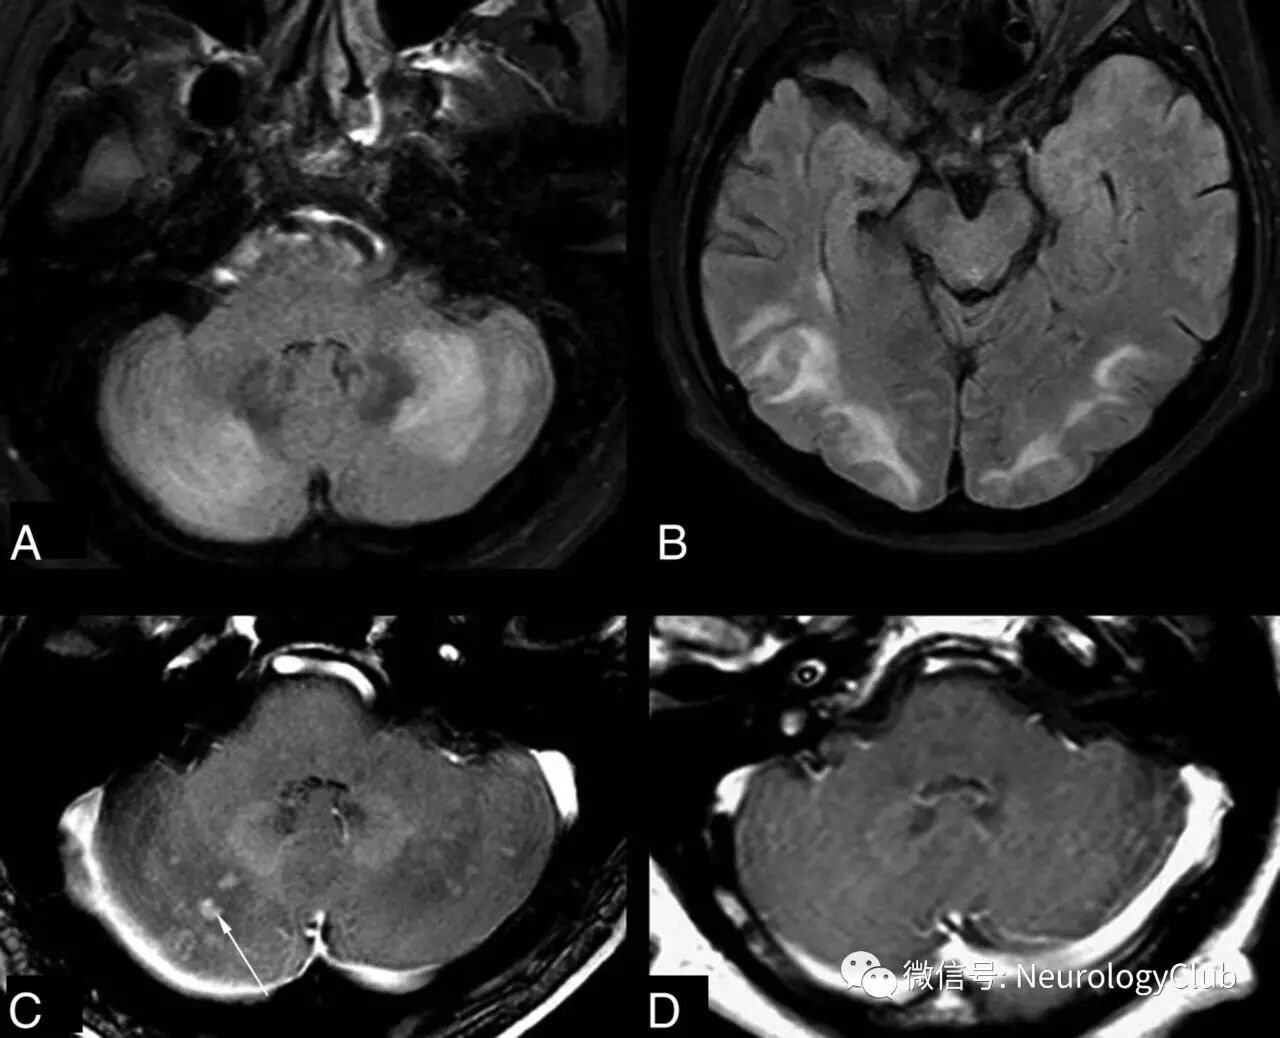

案例3:42岁男性,既往体健,因枕部头痛、恶心、呕吐和失衡入院。血压:190/110mmHg。神经科查体示腱反射亢进,失调步态,双侧轻度辨距不良。入院化验示肌酐9.68mg/dl,尿素氮194.7mg/dl,余无殊。诊断为终末期肾病,予血液透析治疗。2周后临床症状好转。

(图12:起病时MRI表现

(图13:复查时的MRI表现)